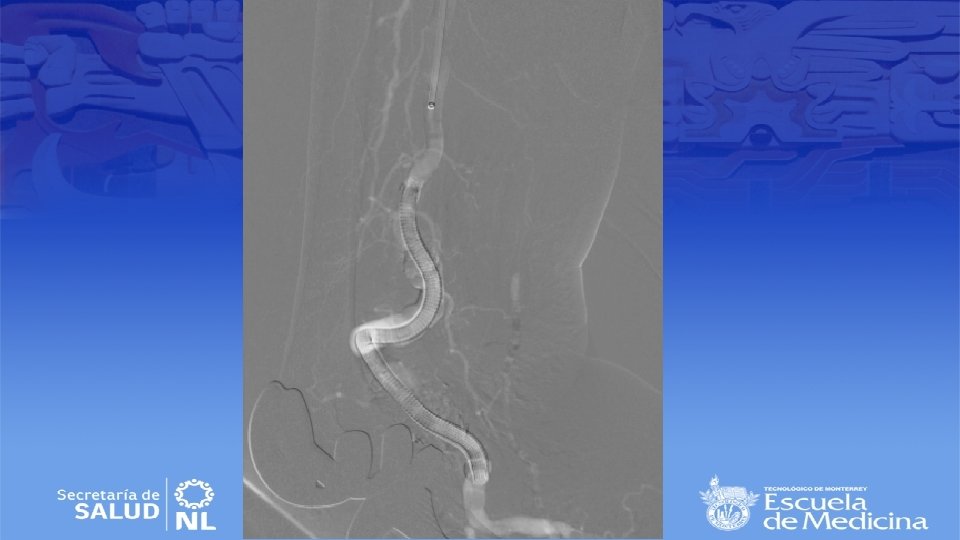

Angiotac

Diagnostico • Ultrasonido Doppler, Angiotac, angioresonancia • Arteriografía es mas apropiada para sintomatología aguda

Cirugía de emergencia • Establecer viabilidad de la extremidad (buscar deficiencia motora o sensitiva) • Sin daño se inicia anticoagulación sistémica y se realiza angiografía en busca de algún vaso viable para bypass. • Si no se encuentran se realiza trombolisis dirigida • Si se encuentra daño el bypass sigue siendo el mejor tratamiento • Si no hay vaso viable se realizara trombectomía tibial

Cirugía endovascular • Para pacientes con alto riesgo quirúrgico • Deben de tener al menos 2 cm de arteria proximal y distal sin patología para anclar la endoprótesis • Se repite la angiografía durante el procedimiento para selección de la endoprótesis correcta • Debe de ser 10 a 15% mas grande que el diámetro del vaso